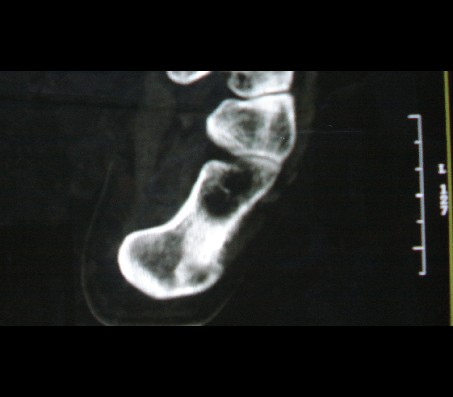

骨髓窦概念:是指松质骨内先天性骨小梁发育稀少,各组骨小梁间的骨小梁少或缺如,形成一空腔,内含有骨髓,称为骨髓窦,为正常解剖变异。骨髓窦以跟骨最多见,简称骨髓窦,其次见于股骨颈、股骨远端及髋臼上缘等处。

形成原因:跟骨窦的形成 跟骨示足弓的重要支点,承受着来自自身及负荷的重量。为了适应承受重量的力学需要,跟骨的结构十分精密合理。其骨小梁的发育有三组:①自跟距关节后缘向后下方呈斜向走行;②沿跟骨下方分布;③自跟结节处向前方伸展。三组骨小梁间有一个类三角形、圆形或椭圆形透亮区,即跟骨窦。

跟骨窦的表现:观察跟骨窦以侧位平片为佳。其特点是位于跟骨前部中央,跟骨沟后方,尖端向上,足弓后上部,承受重量轻的特定位置。窦的基底与跟骨下缘平行。与窦基底相当的跟骨下缘皮质密度高,呈致密带状或线状。窦内骨小梁稀少或缺如。边缘清楚整齐,无硬化。大小1-3cm。窦内有时可见营养沟。多数为单侧,少数双侧对称发生。窦周骨质正常。

鉴别诊断:1.跟骨囊肿 囊肿多位于跟骨后中部,与跟骨窦位置不同。呈圆形或椭圆形,囊内无骨小梁,高度透亮,膨胀生长,周边轻度硬化。2.单房性巨细胞瘤 破坏区边缘清楚,内无骨间隔。骨皮质变薄。临床上有疼痛。肿瘤多位于跟骨后部,肿瘤中心多在跟骨窦之后。3.跟骨结核 病变范围较小,病变呈不规则破坏,边缘模糊,无硬化